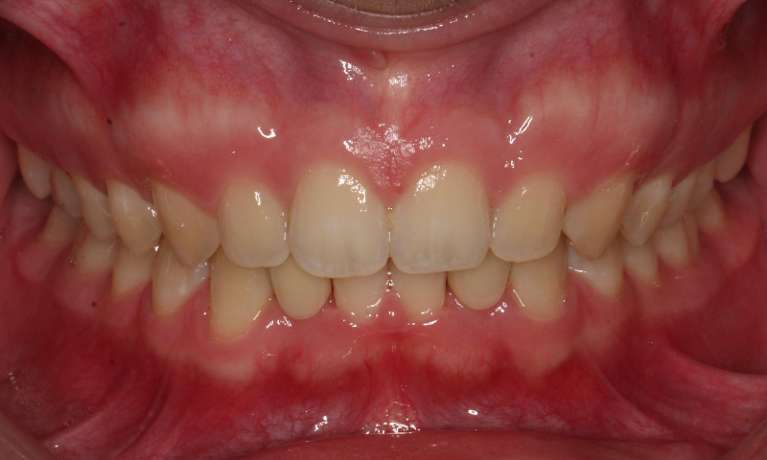

This gallery highlights the treatment of a patient who previously had braces but required additional restoration to close residual gaps. A Maryland cantilever bridge was placed to fill in these spaces, improving both dental function and aesthetics.